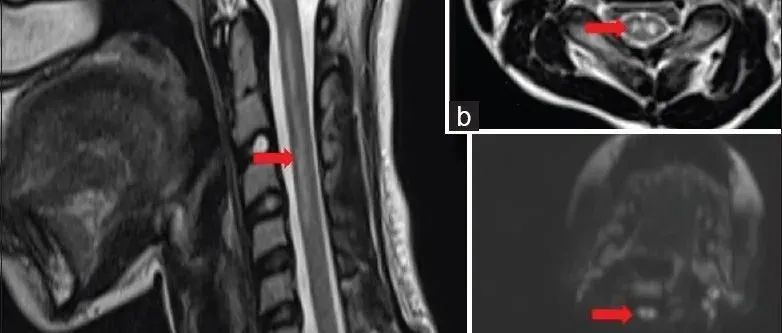

35岁女性,在2次右手局灶性感觉性发作后至医院就诊,其中第2次发展为全面性强直阵挛发作。查体未发现运动或感觉缺陷。MRI可见显示5个幕上病变,最大的2个为囊性病变——左侧中央后回上外侧30×30×32mm和右侧中央后回外侧7×9×6mm。所有病变均为T1低信号和T2高信号,周围有轻度血管源性水肿(图1A和C)。2个囊性病变呈周围强化、FLAIR高信号,且没有弥散限制(见图1B和D)。(图:MRI可见显示5个幕上病变,最大的2个为囊性病变——左侧中央后回上外侧30×30×32mm和右侧中央后回外侧7×9×6mm[A-D];病变呈T1低信号[A]和T2高信号,周围有轻度血管源性水肿[C];其在FLAIR上呈高信号[C],周围中度强化[B],无弥散受限[D];左侧中央后回上外侧病灶活检组织病理学显示脱髓鞘伴有囊性变和明显的星形胶质细胞增生[E],血管周围淋巴细胞成套[F],无残留髓鞘[G],CD163+巨噬细胞[H],以及大量反应性星形胶质细胞[I])...